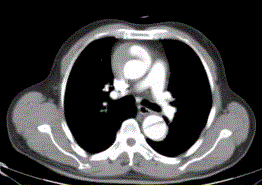

问题 患者男,67岁,高血压病史多年,自服降压药,突发胸骨后剧烈疼痛2h,服用硝酸甘油不缓解。胸透示主动脉增宽。CT影像如下图。 关于内膜瓣,描述正确的是

选项 A.平扫就很容易发现 B.内膜瓣可发现钙化 C.厚度通常大于主动脉壁厚度 D.增强时明显强化故不易显示 E.截面大多呈S型 F.由动脉内膜组成

答案 D

解析 D